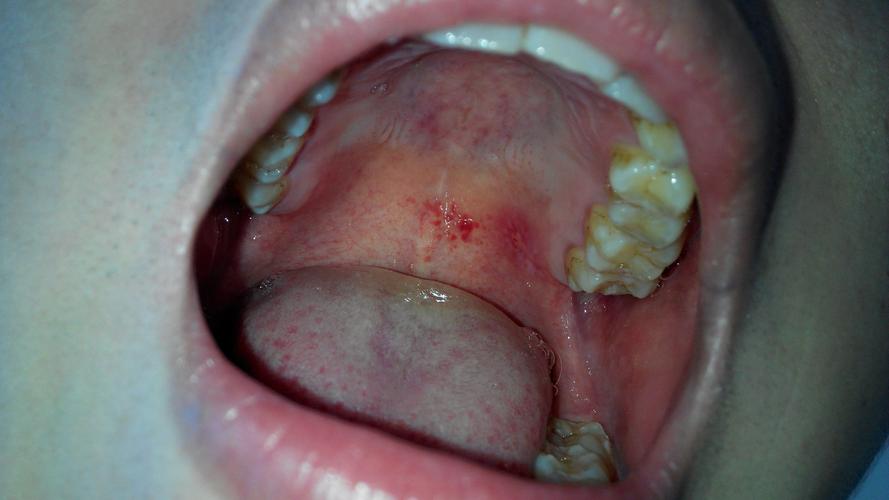

口腔红斑是什么样子的

口腔红斑是什么样子的,口腔红斑图

口腔红斑

(1)口腔黏膜出现的白斑,红斑,黏膜下纤维性变,属于癌前病变.

口腔红斑图

天鹅绒样口腔红斑图片

口腔癌红斑图片

口腔红斑初期症状图片

早期口腔红斑图片

口腔红斑图片